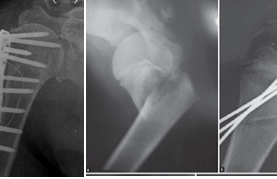

Gãy cổ phẫu thuật xương cánh tay